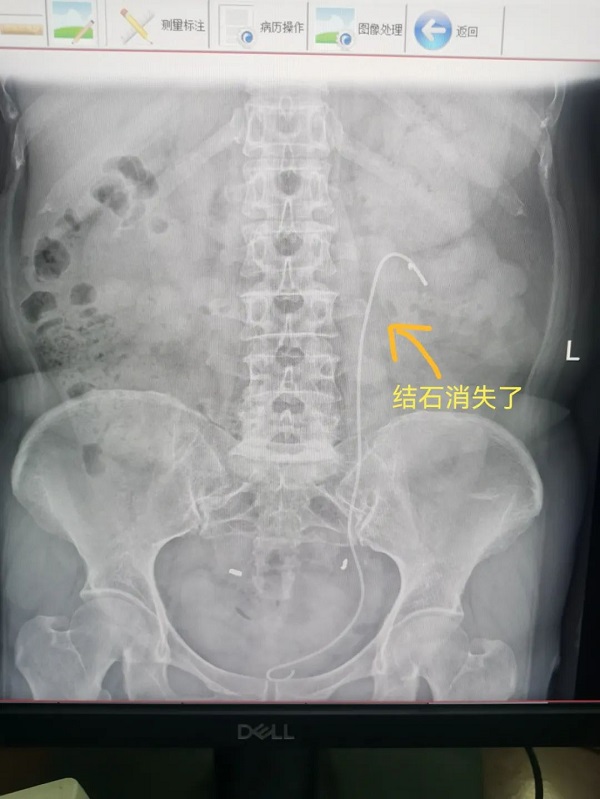

65岁杨大姐和50岁的潘大姐就是这种手术的受益者,她俩均因为腰痛来我院泌尿外科门诊咨询就诊,医生诊断为肾结石,并建议她们做输尿管软镜手术治疗,通过医生的详细介绍,杨大姐和潘大姐对这种没有任何刀口的手术方式表示很惊讶,紧张的心情一下子就放松了。

通过应用负压吸引鞘,主任医师辛明辉、副主任医师刘伟带领泌尿外科团队在麻醉医师的通力合作下,对结石进行了完全清除,手术均顺利完成。经过术后康复,杨大姐和潘大姐在手术后第三天就顺利出院了。